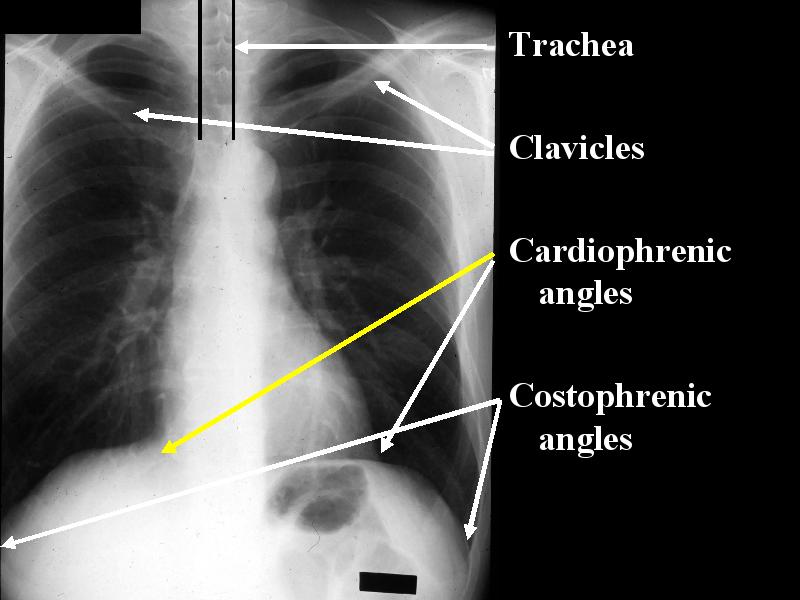

MS 202 CXR NL PA